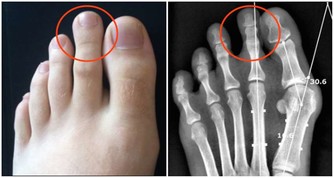

脊椎支撐著人體的上半部,對於身體健康有很大的影響,也是反映其他病痛的指標,而且背痛可不是鬧著玩的。無論生活習慣是否良好,我們都必須好好照顧自己的身體,然而要如何避免脊椎受傷或擺脫背部疼痛的風險,其實有七招日常生活中就可以執行的方式,能夠減少脊椎遭受破壞的可能性,快來看看要怎麼做吧。 廣告- ▼如果經常腰酸背痛,很有可能是你的脊椎出了問題而不自知。